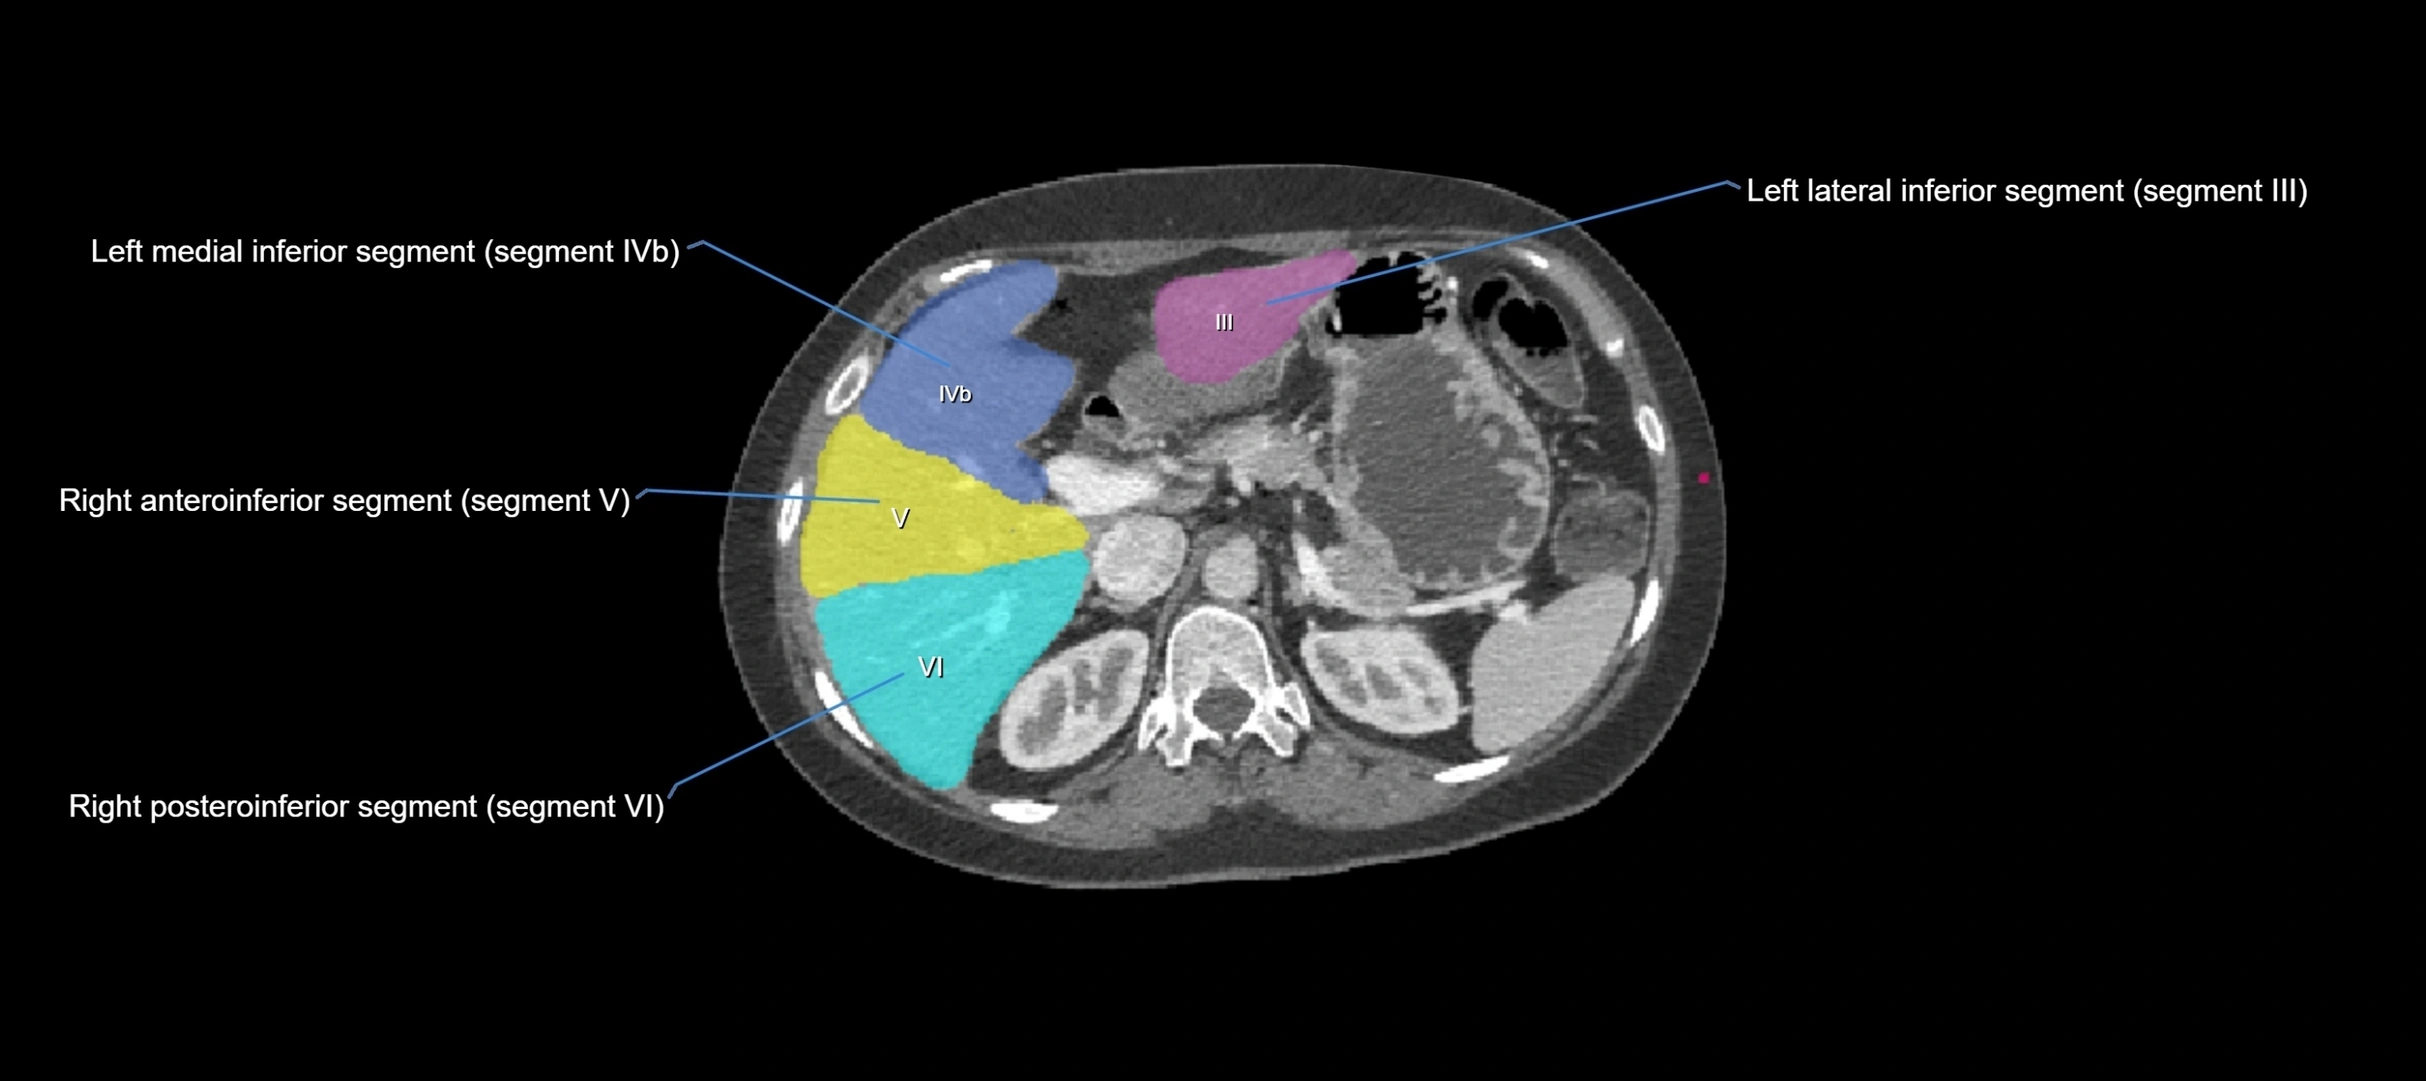

CT Image

image